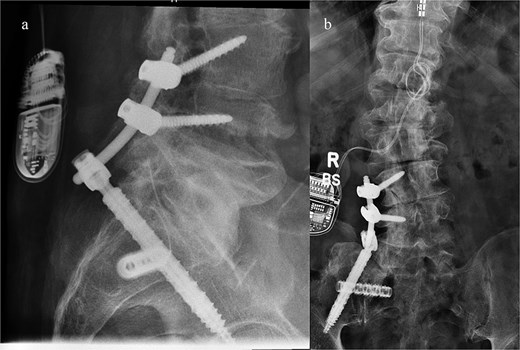

Next, a minimally invasive right SI joint bolt was placed. A second, 1-in. incision was made over the right lateral iliac fossa. A navigated drill was used to cannulate a pilot hole through the right ilium, crossing the sacroiliac joint, into the right sacral ala. A 12 mm tap was then used, and a 12 mm diameter, 50 mm length Rialto SI joint fusion implant was inserted across the right sacroiliac joint. A final O-arm scan was performed to confirm good position of all implants (Fig. 3).

Intraoperative O-arm spin confirmed placement of the right L4 and L5 pedicle screws, as well as the right iliac screw and right sacroiliac implant. The left-sided navigation clamp can be visualized. The patient’s spinal cord stimulator (seen in the figure) was carefully avoided. One can also see the pronounced osseous abnormality along the right lower spine, extending to the sacrum and medial ilium.